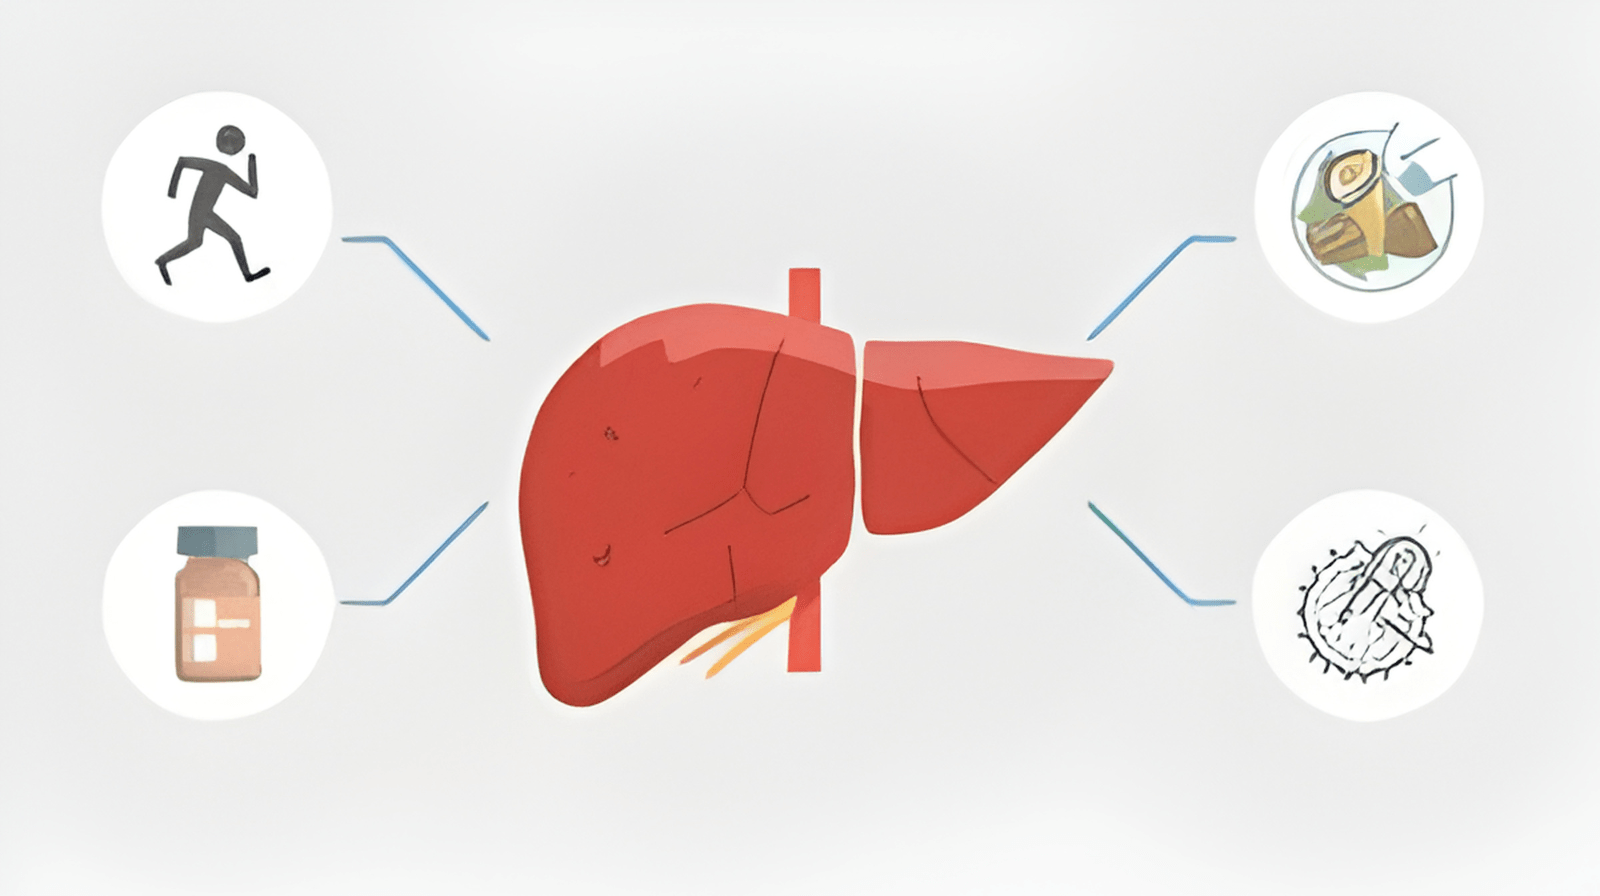

Treatments for MASLD (Metabolic dysfunction-Associated Steatotic Liver Disease)

Non-Alcoholic Fatty Liver Disease is increasingly common worldwide and linked to obesity, diabetes, and metabolic syndrome. Recent research underscores that MASLD treatment centers on lifestyle modification and drug therapies targeted at metabolic risk factors.